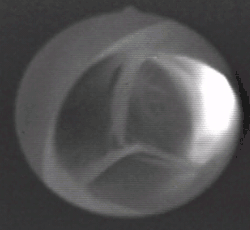

Net als de pulmonalisklep (valva trunci pulmonalis) die functioneert tussen rechterhartkamer en longslagader, bestaat de aortaklep uit drie halvemaanvormige zakjes, slippen genaamd, met de opening van het zakje in de richting van de aorta. Tijdens de systole, wanneer de linkerhartkamer samentrekt, worden deze zakjes plat langs de wand gedrukt en staat de klep open. Als de kamer zich geheel geleegd heeft en zich ontspant, duwt het bloed uit de aorta de zakjes open, die met zijn drieën de aorta dan volledig afsluiten. Dit sluiten van de aortaklep is met de stethoscoop te horen en vormt samen met de pulmonalisklep, die bijna gelijktijdig sluit, de tweede harttoon. Het geluid dat ontstaat is afkomstig van de trilling van de wanden door het sluiten van de kleppen. De aortaklep ligt iets rechtsachter de pulmonalisklep. De aorta vormt vervolgens een boog, die van rechtsvoor over de rechterlongslagader heen buigt en links van het midden afdaalt naar borst, buik en benen.